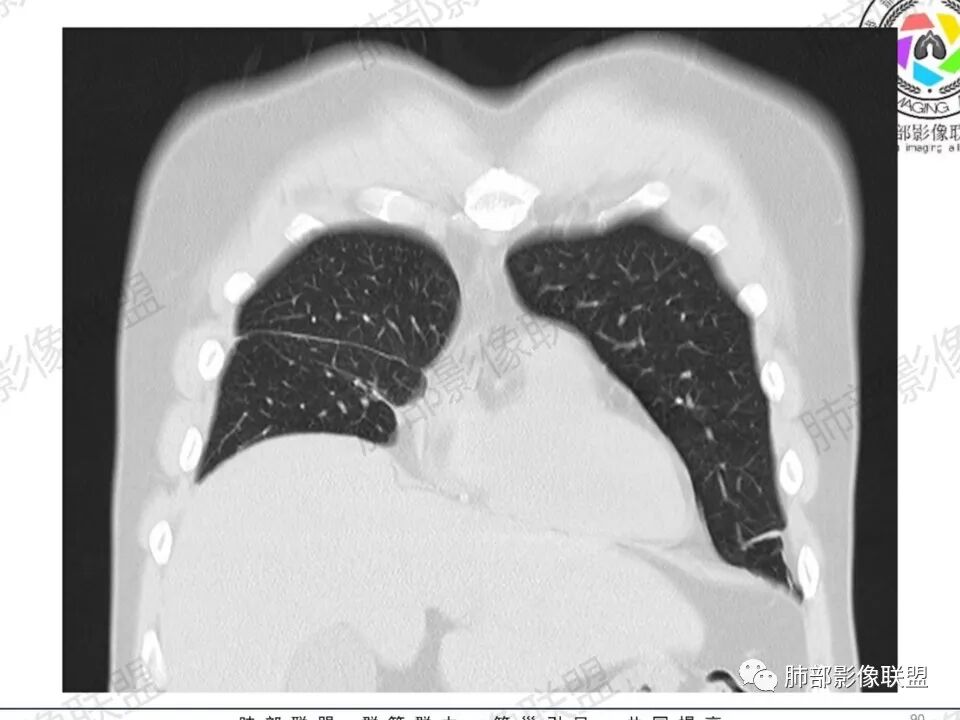

双肺多发结节,胸膜下为主,部分可见空洞。左肺上叶尖后段结节较大,分叶毛刺,周围可见长条索及小斑片影,内空洞比较光滑,内侧壁可见支气管通过。右肺下叶后基底段不张实变,后侧积液,右侧水平裂积液,右侧膈胸膜纵膈胸膜增厚积液,右侧侧胸膜肥厚,考虑1:一元金葡。2二元:金葡,左肺上叶结核。

中年男性,左手中指及胸壁疼痛伴发热来诊,影像见双肺多发结节,胸膜下分布为主,部分结节可见空洞,边缘模糊。左肺上叶尖后段结节较大。右肺下叶后基底段不张实变,右侧叶间裂及右侧胸腔积液,右侧侧胸膜肥厚。考虑金葡菌感染,血播SPE。

两肺多发结节空洞,随机分布,右肺下叶部分病灶实变并胸膜腔少量积液,有皮肤破溃,手指疼痛,发热,考虑感染性变,金葡可能性大。

胸膜下为主多发结节,边缘光滑

伴随楔形影,支气管壁不增厚

胸水,部分包裹